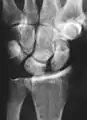

Eventually, untreated scapholunate instability generally causes a predictable pattern of wrist osteoarthritis called scapholunate advanced collapse (SLAC).[2]